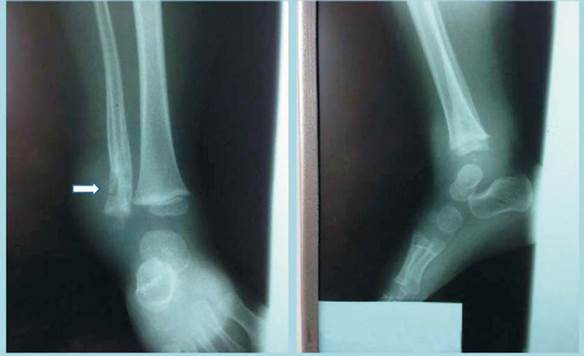

Se solicita radiografía de la articulación tibiotarsiana derecha observándose múltiples imágenes geódicas que afectan la cortical del sector distal de la diáfisis del peroné, con pequeño secuestro óseo en su interior. Engrosamiento del periostio de ambas corticales proximales a las lesiones (Figura 1). La radiografía del miembro inferior contralateral no muestra alteraciones.